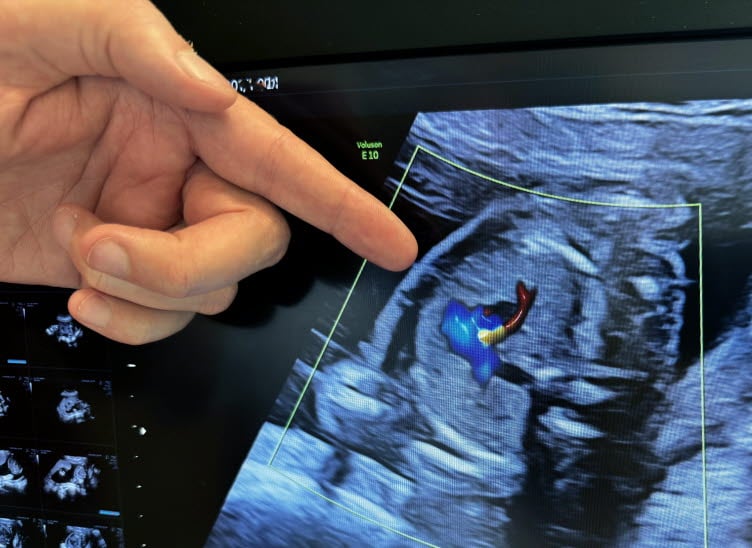

Robert Råman beskriver sig själv som tekniknörd. Just ultraljudsapparaten är en dröm med alla inställningar och möjligheter.

– De flesta andra läkare blir stressade av en gravid patient eftersom det försvårar bedömningen och behandlingen. Det går inte att se det gömt där i magen eller säga hur det mår. Men här är vi trygga tack vare ultraljud och CTG som mäter barnets hjärtfrekvens men även hur det reagerar med sitt autonoma nervsystem.

Robert beskriver ultraljudet som att lyfta på locket på en rysk docka. Att kika in och se hur barnet har det är fascinerande. Maskinerna är som en stor dator med många inställningsmöjligheter. Det blir lite nörderi om man gillar teknik.

Fostervatten och njurar

När Robert Råman tittar in på barnet i magen är främsta syftet att fastställa mående och tillväxt. Han mäter huvud, buken och låret för att via en formel uppskatta storleken. Rörelsemönstret studeras liksom fostervattnets nivå som indikerar njurarnas och moderkakans funktion. Även blodflöden visar om barnet har det sämre i magen än det skulle ha utanför. Det är uppgifter som leder till beslut om i vilket skede det är dags att förlösa.